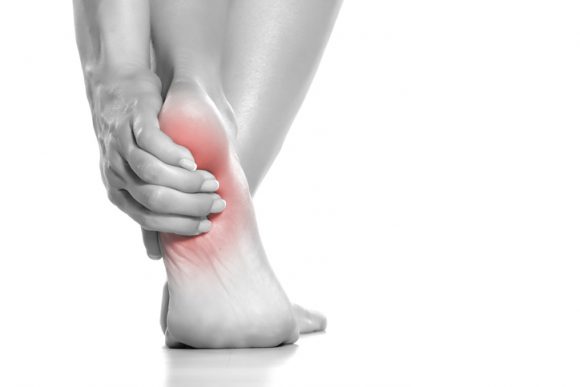

플랜타르 패시아염 (족저근막염)

- 발바닥의 아치에 위치한 두꺼운 섬유 조직인 족저근막이 염증이 생기는 질환입니다. 주로 장시간 서 있거나 걷는 경우, 혹은 비만으로 인해 과도한 압력이 가해져 발생합니다. 통증은 주로 아침에 일어났을 때 첫 발을 내딛을 때 가장 심하게 느껴지며, 점차 운동 후에도 나타날 수 있습니다.